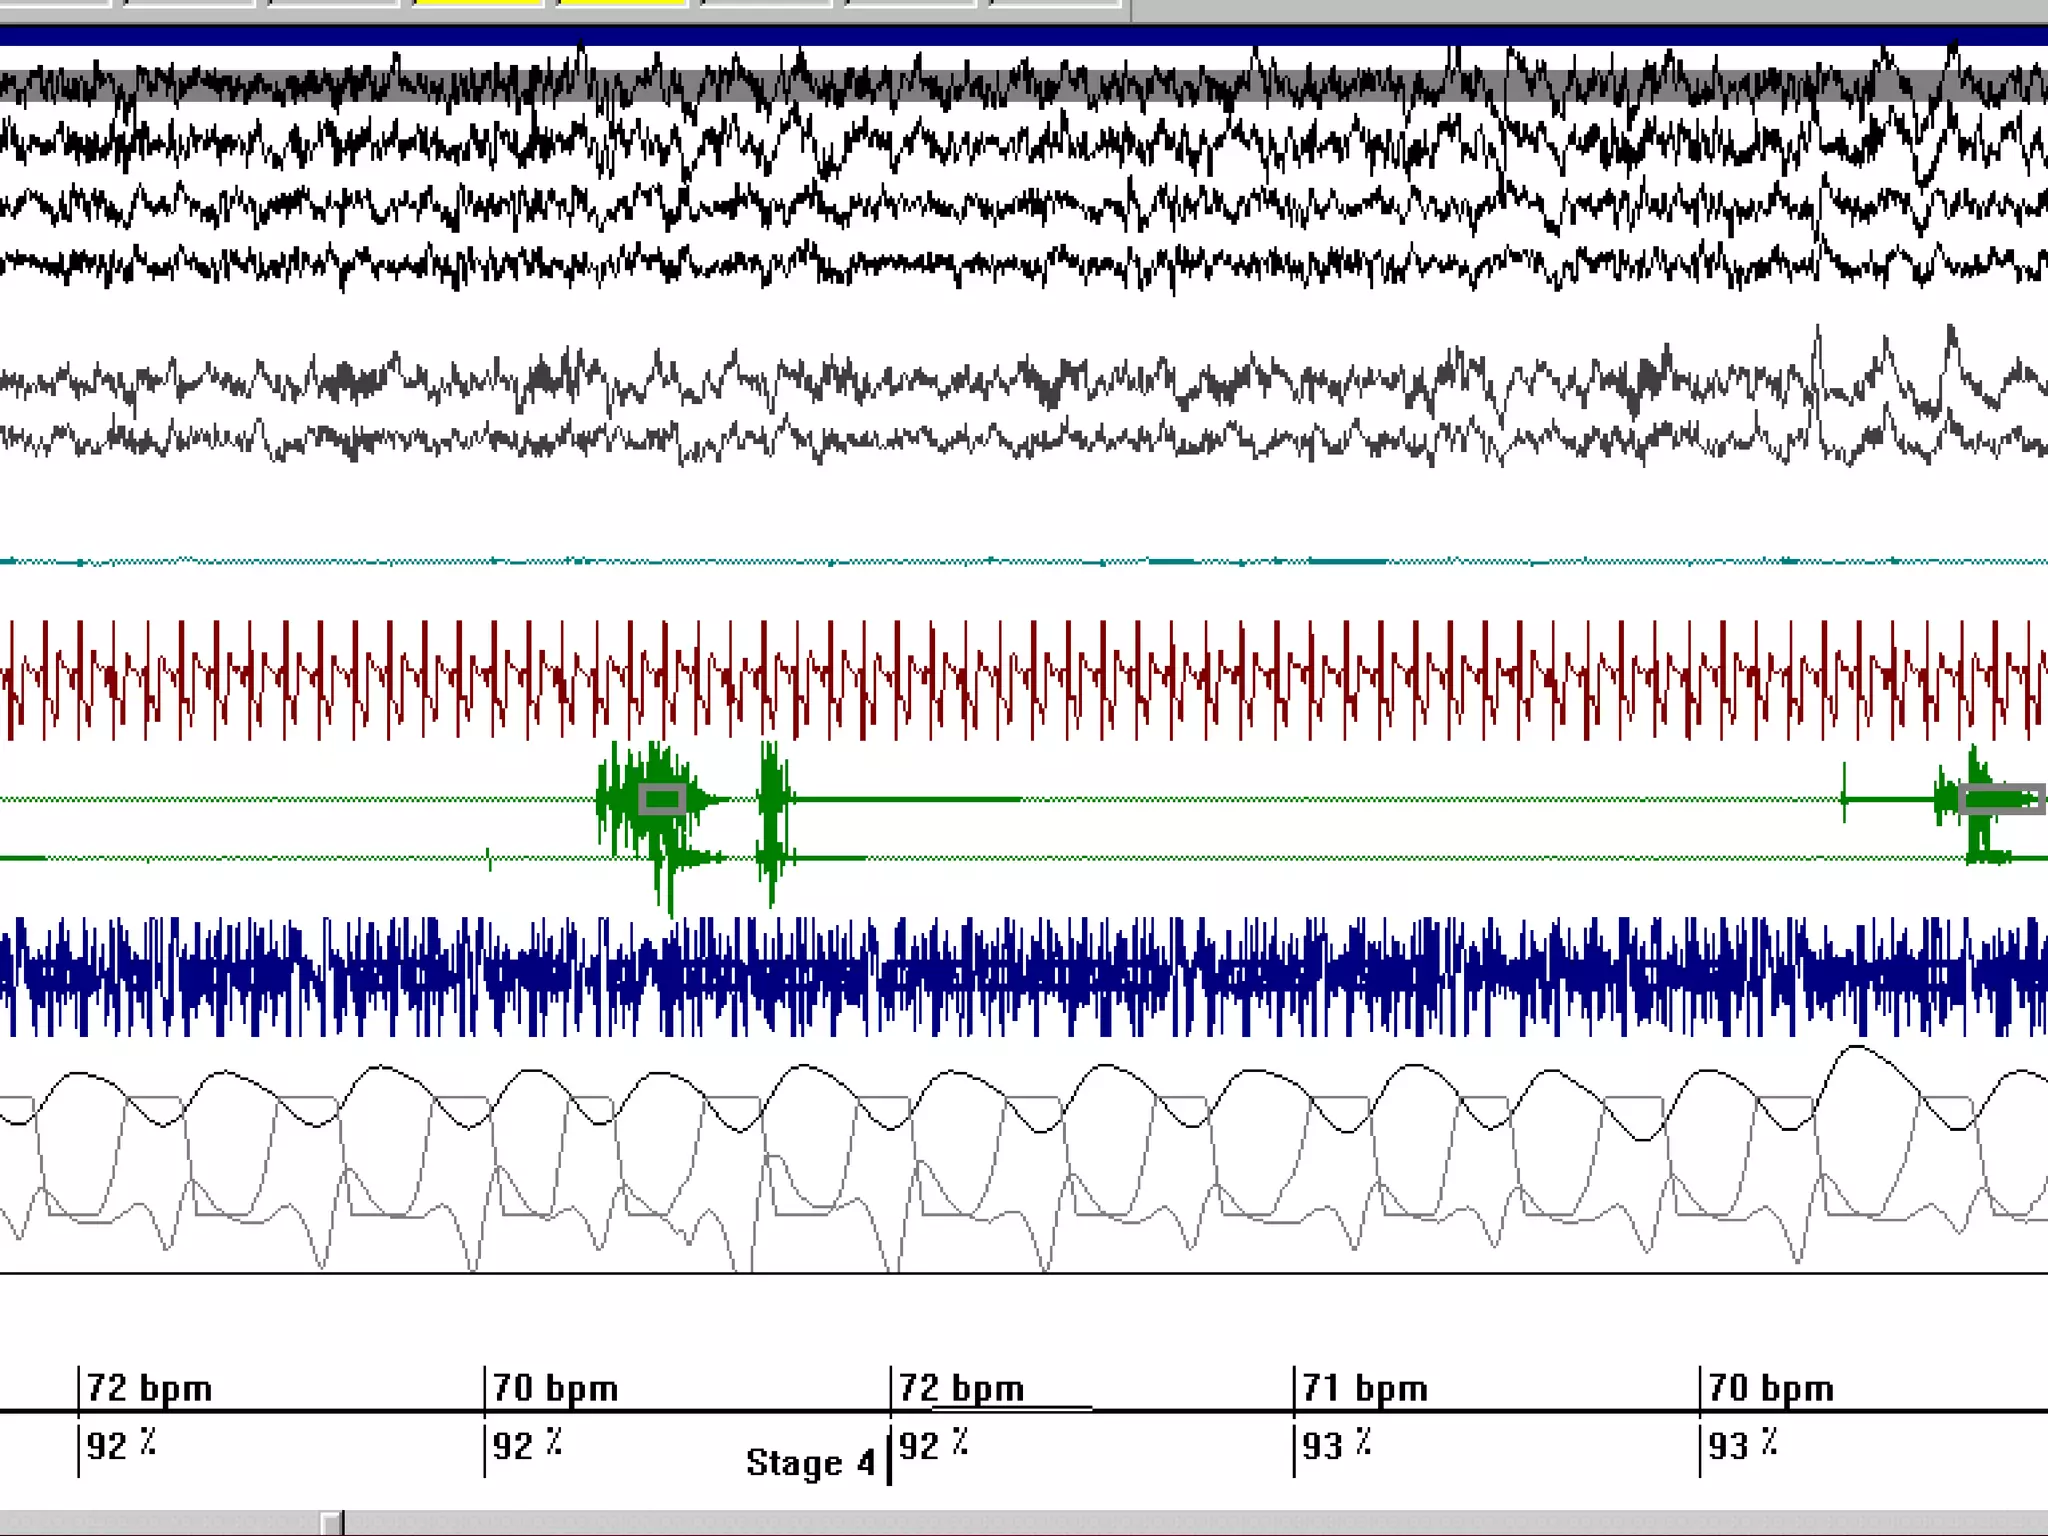

Polysomnography

Polysomnography is a simultaneous

recording of multiple physiologic

parameters related to sleep and wakefulness

– EEG

– EOG

– EMG

Parameters monitored:

1-Four (EEG) channels

2-Two  (EOG) channels

3-One (EMG) channel

4-Airflow( nasal and

oral) for the detection

of apnea

5-Sound recordings to

measure snoring

6-ECG

7-Pulse oximetry

8-Respiratory effort (Thoracic

and abdominal belts)

9- Tibialis anterior EMG

10-Detector of the body

position

11-Esophageal manometry

Neurologic monitoring Techniques •Extended EEG ( 12-36) channel • Repeated studies ,video monitored DD: • Nocturnal seizures • Parasomnias • REM behavioral disorders